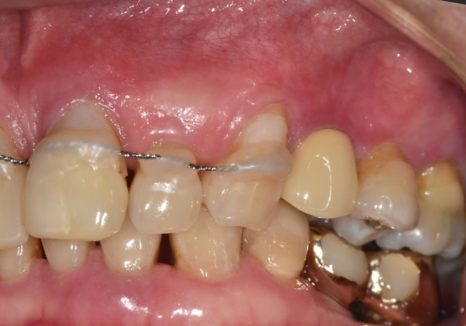

앞니가 너무 흔들리다 보니,

흔들리는 앞니 3개를

왼쪽 송곳니에 철사로

연결(스플린트) 해서 생활하고 계셨어요.

스플린트는 쉽게 말하자면,

흔들리는 치아들을

튼튼한 옆 치아랑 한 덩어리로 묶어서

힘을 나눠 받게 하는 방법입니다.

250106 스플린트로 묶인 치아

잠깐은 버틸 수 있지만,

근본 문제가 해결된 건 아니죠.